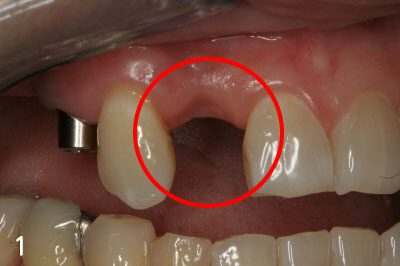

Bone Graft

Gum bone is depressed after extraction

Performing implant placement and bone graft

Implant crown is fabricated after successful bone graft and implant placement